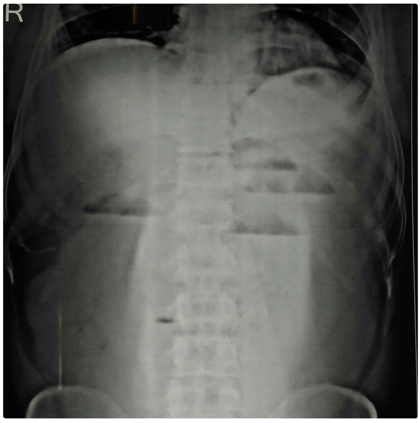

X-ray of the abdomen in erect posture showed multiple air-fluid levels (Figure 1) and ultrasonography revealed the presence of right sided inguinal hernia containing aperistaltic loops of intestine with fluid collection (Figure 2). So a diagnosis of right sided obstructed inguinal hernia was made on the basis of clinical and radiological finding. The patient was planned for surgery on an emergency basis.

Figure 1: X-ray of the abdomen in erect posture showed multiple air-fluid levels.